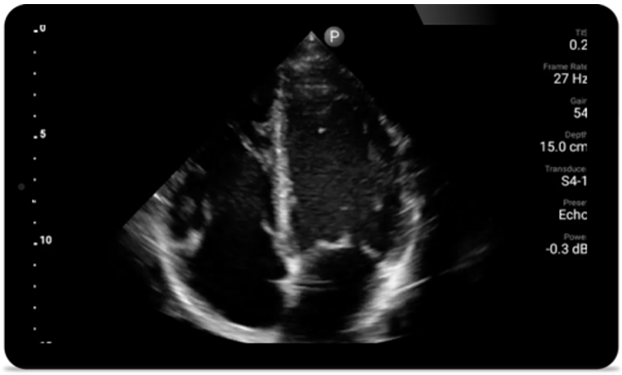

Every second counts

in cardiac care

Heart attack patients need immediate care.

Lumify's cardiac presets can help patients get

diagnosed faster to improve their outcomes.

Broadband phased array transducer

Lumify S4-1 broadband phased array transducer

• 4 to 1 MHz extended operating frequency range

• 2D, color Doppler, M-mode, advanced XRES and multivariate harmonic imaging

• High-resolution imaging for abdominal and cardiac applications: Cardiac, OB/GYN, Lung, Abdomen and FAST imaging preset optimizations Lumify aids life-saving technology in prehospital setting